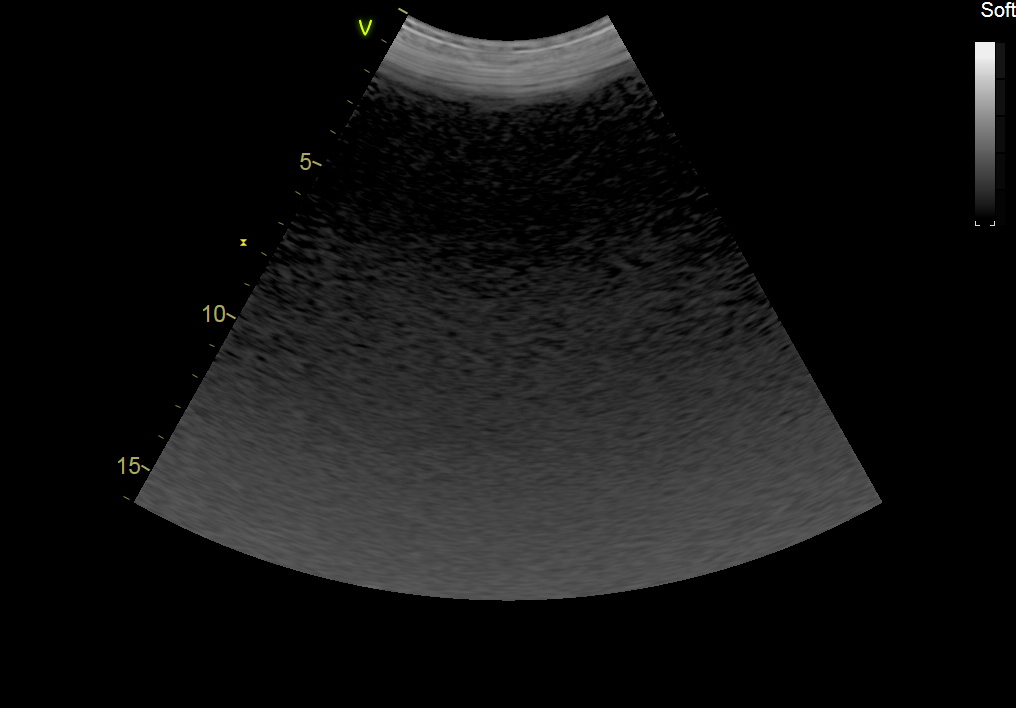

GE C1-6-D Abdominal Convex Refurbished

GE Convex C1-6-D Abdominal

Intended use

Abdominal and Women’s Health

Frequency Range

6 – 1 MHz

GE C1-6-D Abdominal Convex

Frequency Range: 6 – 1 MHz

GE C1-6-D Abdominal Convex for Abdominal and Women’s Health